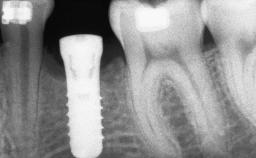

| # of Implants | 3 |

| Bone Augmentation | Horizontal|Staged|Vertical |

| Placement Protocol | Early or late implant placement |